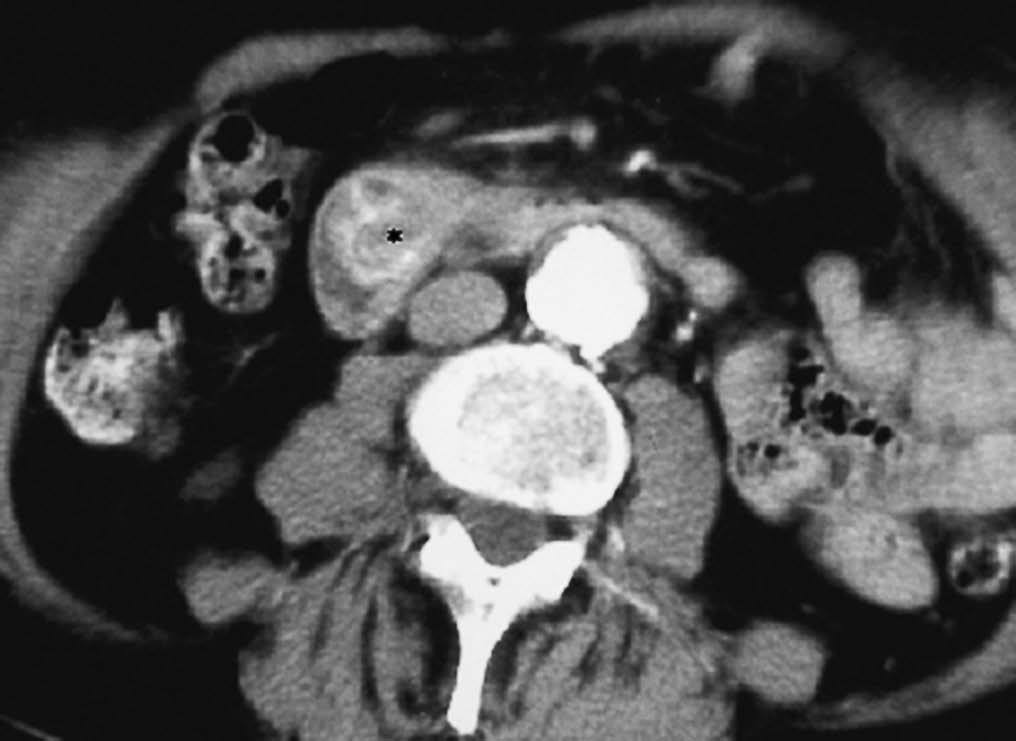

La pancreatitis del surco, región anatómica situada entre la cabeza del páncreas, duodeno y colédoco, es una lesión fibrosa que oblitera el plano graso de separación entre la pared duodenal y el páncreas. Puede provocar una estenosis de la luz duodenal y del colédoco. Radiológicamente simula un cáncer pancreático, manifestándose en la ecografía como una lesión hipoecoica y en la TC como imagen hipodensa, hipovascular en la fase precoz, con realce tardío18,19 (fig. 12).

Fig. 12--Pancreatitis del surco. Tomografía computarizada con contraste intravenoso. Lesión hipodensa (*), mal definida, que oblitera el plano graso normal entre páncreas (P) y duodeno (D) y con escaso realce.